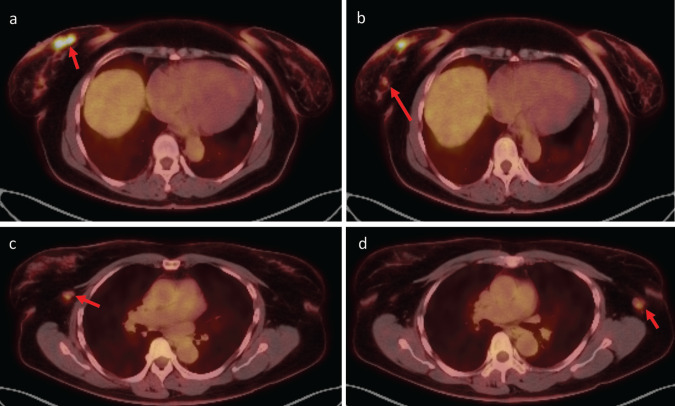

Rosai-Dorfman disease (RDD) is a self-limited, idiopathic, non-neoplastic disorder characterized by the proliferation of phagocytic histiocytes, which can mimic malignant lymphoproliferative disease. Cases of RDD most commonly present as bilateral painless cervical lymphadenopathy, with lesser involvement of the axilla, inguinal, and mediastinal lymph nodes. We present the case of a 62-year-old woman with a history of endometrial serous carcinoma who underwent evaluation at a dedicated breast imaging department after positron emission tomography/computed tomography (PET/CT) revealed breast masses and axillary nodes with increased uptake of fluorodeoxyglucose (FDG). Upon clinical examination, she had bilateral palpable lumps in both breasts and axillae. Subsequent dedicated breast imaging with bilateral diagnostic mammography with tomosynthesis and bilateral complete breast ultrasound were suspicious for malignancy detecting bilateral breast masses and axillary lymphadenopathy corresponding to the FDG-avid findings on PET/CT. Ultrasound-guided core needle biopsies, however, revealed a diagnosis of RDD. This case highlights the unique characteristics of RDD with an atypical clinical presentation suspicious for breast cancer both clinically and radiologically.